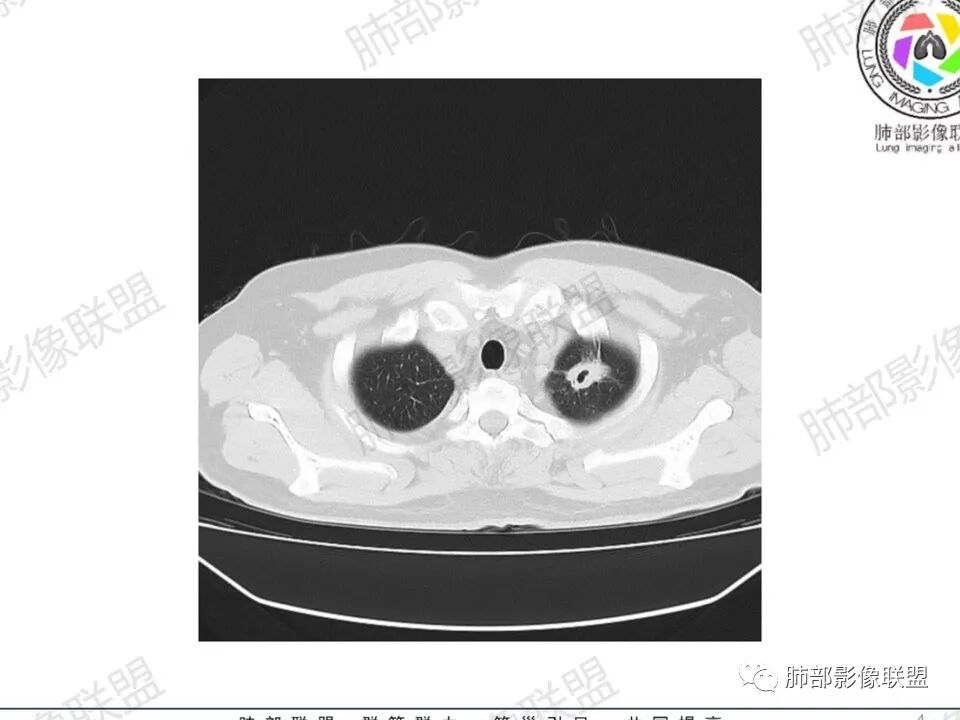

双肺多发结节,胸膜下为主,部分可见空洞。左肺上叶尖后段结节较大,分叶毛刺,周围可见长条索及小斑片影,内空洞比较光滑,内侧壁可见支气管通过。右肺下叶后基底段不张实变,后侧积液,右侧水平裂积液,右侧膈胸膜纵膈胸膜增厚积液,右侧侧胸膜肥厚,考虑1:一元金葡。2二元:金葡,左肺上叶结核。

尘缘: @赵永兵 内蒙巴市临河妇幼影像科 左上肺也是胸膜下(胸膜顶下)的SPE。

@赵永兵 内蒙巴市临河妇幼影像科 支气管是从旁边经过,所以不是空洞,是胸膜下的脓毒栓。如果是结核空洞,应该与支气管相通(因为结核没有血播感染表现的时候,来源是气道,空洞应该与支气管相通),所以支气管从旁边经过,这病灶又在胸膜下,周围也没有干酪坏死。当然是SPE了。

中年男性,左手中指及胸壁疼痛伴发热来诊,影像见双肺多发结节,胸膜下分布为主,部分结节可见空洞,边缘模糊。左肺上叶尖后段结节较大。右肺下叶后基底段不张实变,右侧叶间裂及右侧胸腔积液,右侧侧胸膜肥厚。考虑金葡菌感染,血播SPE。

胸膜下为主多发结节,边缘光滑

伴随楔形影,支气管壁不增厚